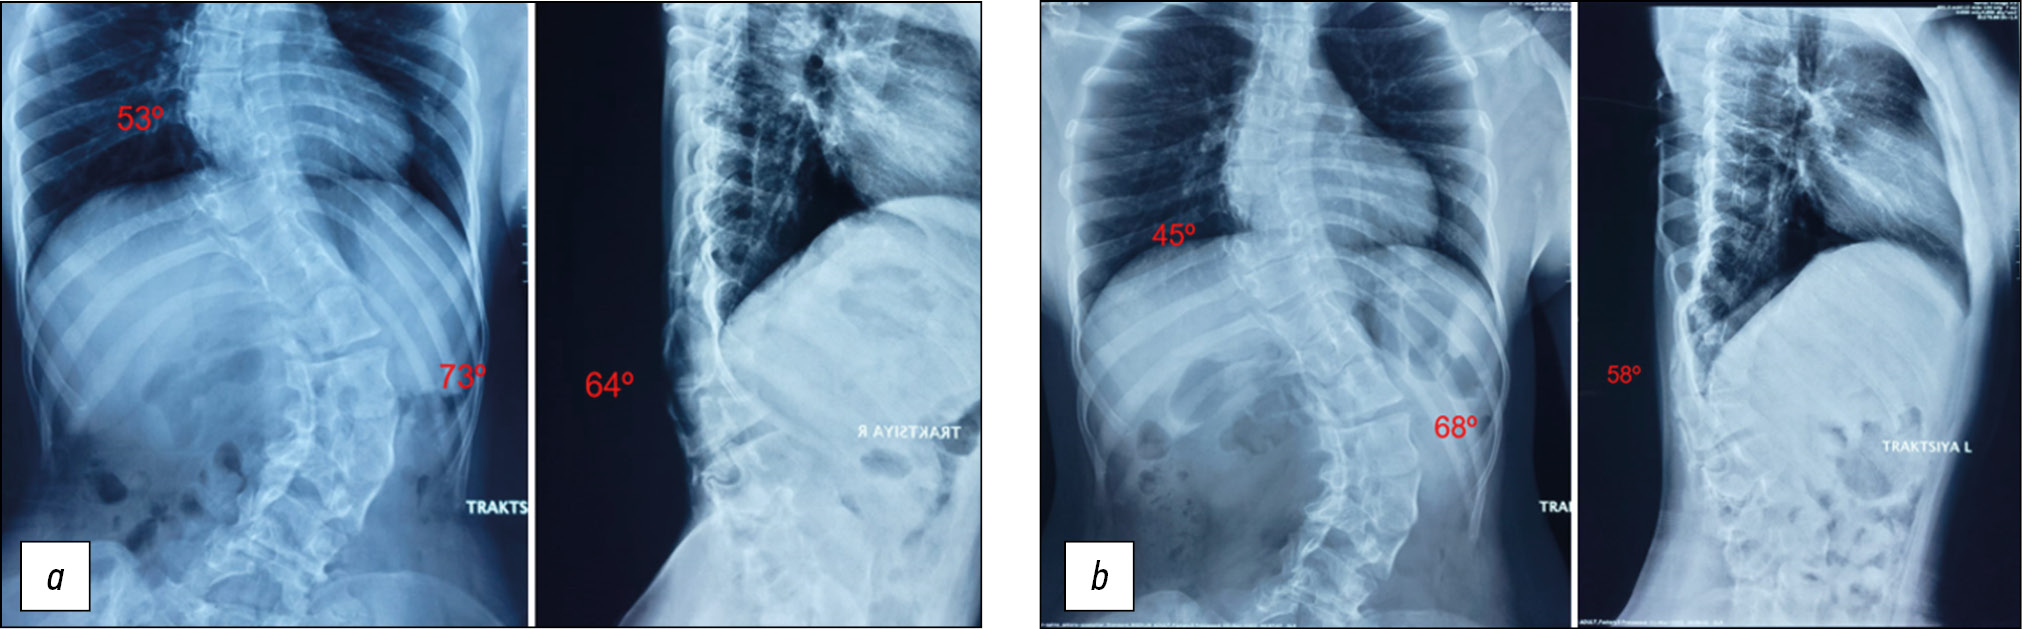

During the preoperative planning stage, the patient underwent a traction test, and the magnitude of the deformity angles was corrected to 53°, 73°, and 64°, respectively. The thoracic mobility index (MI) was 0.76, the lumbar mobility index (MI) was 0.81, and the local kyphosis index was 0.88. A CT scan was also performed, from which a 3D spine model was printed, and areas of previous surgical interventions (laminectomy) were visualized, where potentially high risks of dural membrane damage when approaching posterior elements existed (Fig. 2).

Because of the severity of the deformity, its rigidity, the revision of the surgical intervention, and the high risk of neurological complications with simultaneous correction, it was decided to perform preoperative halo-gravitational traction in a chair and a walking frame in conjunction with mobilizing ET at stage 1, and interventions to correct and stabilize the spine at stage 2. Traction was established in the chair at a sitting posture the next day after the halo ring was installed. After 3 days, dosed halo-traction was added in a walking frame. From the first day following ring installation, the patient began to visit the gym, where ET sessions were performed according to an individual program to mobilize the spine, increase muscle strength of the back extensor muscles, and improve the functions of external respiration. There were 28 days of traction, with 12 ET sessions. The patient was checked daily for neurological traction complications. After preoperative halo-gravitational preparation and ET, a traction test of the spine was performed again, and the magnitude of scoliotic curves decreased to 45° (MI=0.64) in the thoracic region and 68° (MI=0.76) in the lumbar region, whereas local kyphosis decreased up to 58° (MI=0.79; Fig. 3).

Fig. 3. Functional radiographs of traction tests (a) before the preoperative preparation and (b) after its completion in 28 days.